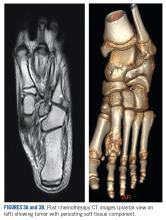

A 10-year-old girl visited our outpatient clinic with a painful progressive swelling on the dorsum of the left foot of 2 months’ duration. There was no history of antecedent trauma or fever. Physical examination revealed a bony hard swelling measuring around 5 x 6 cm on the dorsum of the left foot around the region of the second metatarsal. There was no regional lymphadenopathy or distal neurovascular deficit. She was evaluated with a plain radiograph that demonstrated a lytic lesion in the left second metatarsal associated with cortical destruction and periosteal reaction (Figure 1) . A subsequent magnetic resonance image (MRI) revealed a bony lesion destroying part of the left second metatarsal with cortical destruction and marrow involvement and affecting the soft tissue around the adjacent third metatarsal (Figure 2) . Needle biopsy showed chondroblastic osteosarcoma. Computed tomography (CT) of the thorax and bone scan were both negative for distant metastases.